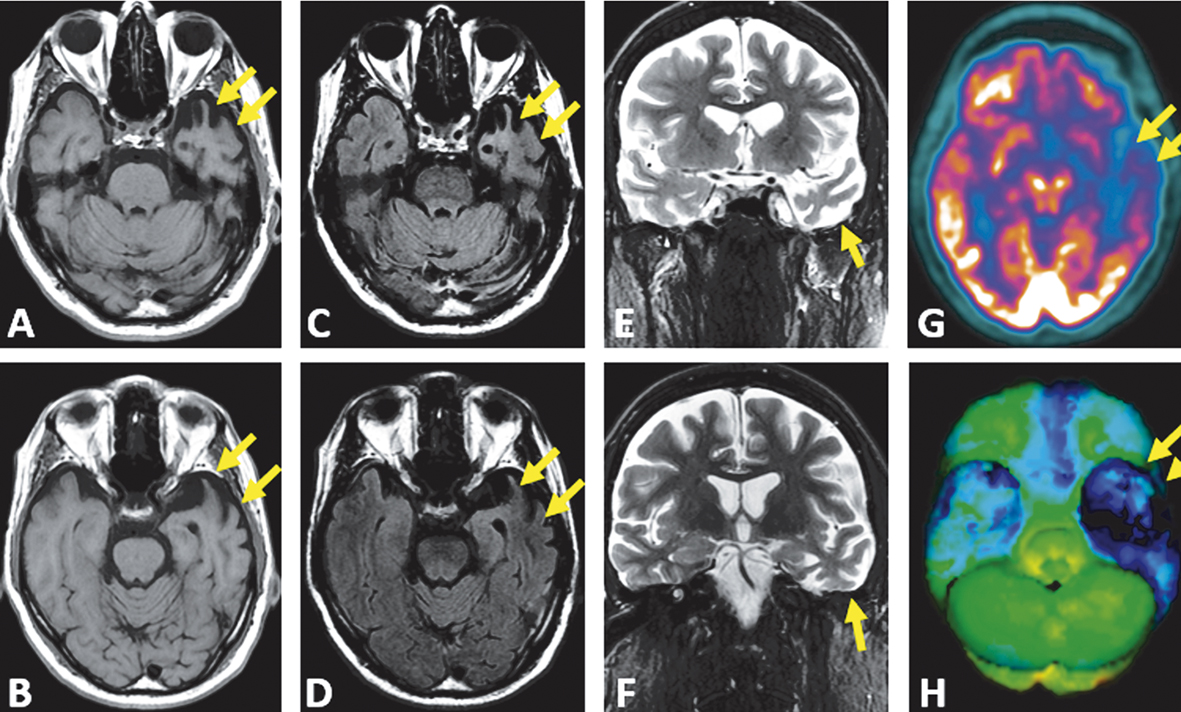

Imagens axiais T1 (A e B) e FLAIR (C e D) e imagens coronais T2 (E e F). Imagens de PET-FDG axial (G) e reconstrução 3D (H). Nota-se atrofia desproporcional do polo temporal esquerdo (setas). Os giros estão afilados e os espaços liquóricos, alargados. Nas imagens FLAIR, destaca-se o hipersinal da substância branca com perda da diferenciação corticossubcortical. O estudo de PET-FDG evidencia importante hipometabolismo do lobo temporal esquerdo (setas), com comprometimento menos relevante do lobo temporal contralateral e dos lobos frontais.

Os estudos de imagem têm papel fundamental em tais casos, uma vez que participam dos critérios de diagnóstico. O padrão da imagem tipicamente associado a essa condição é de atrofia ou hipometabolismo do polo temporal do hemisfério dominante – o esquerdo, na maioria dos indivíduos acometidos. No contexto clínico apropriado, a identificação de sinais de atrofia seletiva dessas regiões permite identificação da variante semântica da APP suportada por imagem.